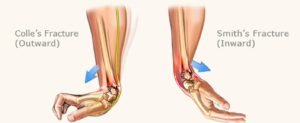

Κάταγμα Colles

Εξωαρθρικό κάταγμα κάτω επίφυσης κερκίδας με ραχιαία παρεκτόπιση (παραμόρφωση πιρουνιού) . Δημιουργείται μετά από πτώση επάνω στην ανοικτή παλάμη.

Κάταγμα Smith

Εξωαρθρικό κάταγμα κάτω επίφυσης κερκίδας με παλαμιαία παρεκτόπιση . Δημιουργείται μετά από πτώση σε κλειστή παλάμη.

Eικόνα : Απεικόνιση των καταγμάτων colles , smith . Διαθέσιμο στον διαδικτυακό ιστότοπο :